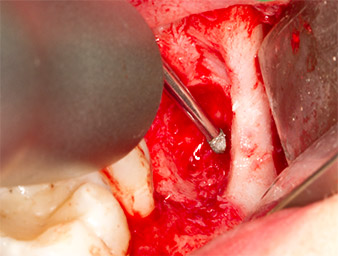

The tissue above the root remnant was not completely ossified and consisted for the most part of granulation tissue modified by inflammation (Fig. 4).

To obtain autogenous material for subsequent wound treatment, healthy bone chips were harvested from the surroundings of the root remnant with a piezo surgical instrument (Piezomed B5) (Fig. 5).

Granulation tissue

Fig. 4: Two Langenbeck retractors and a raspatorium expose the operating area. Granulation tissue of the incompletely healed first osteotomy can be seen.

Piezomed B5

Fig. 5: Bone in the region of the alveole is lifted with a chisel-shaped piezo surgical instrument (Piezomed B5). This bone is used as autologous augmentation material after removal of the root remnant (cf. Fig. 13 and 14).